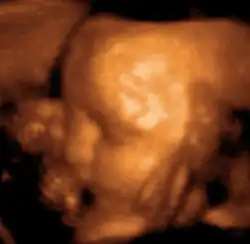

Medical ultrasound is an ultrasound-based diagnostic medical imaging technique used to visualize muscles, tendons, and many internal organs to capture their size, structure and any pathological lesions with real time tomographic images. Ultrasound has been used by radiologists and sonographers to image the human body for at least 50 years and has become a widely used diagnostic tool.[38] The technology is relatively inexpensive and portable, especially when compared with other techniques, such as magnetic resonance imaging (MRI) and computed tomography (CT). Ultrasound is also used to visualize fetuses during routine and emergency prenatal care. Such diagnostic applications used during pregnancy are referred to as obstetric sonography. As currently applied in the medical field, properly performed ultrasound poses no known risks to the patient.[39] Sonography does not use ionizing radiation, and the power levels used for imaging are too low to cause adverse heating or pressure effects in tissue.[40][41] Although the long-term effects due to ultrasound exposure at diagnostic intensity are still unknown,[42] currently most doctors feel that the benefits to patients outweigh the risks.[43] The ALARA (As Low As Reasonably Achievable) principle has been advocated for an ultrasound examination – that is, keeping the scanning time and power settings as low as possible but consistent with diagnostic imaging – and that by that principle nonmedical uses, which by definition are not necessary, are actively discouraged.[44]

Ultrasound is also increasingly being used in trauma and first aid cases, with emergency ultrasound being used by some EMT response teams. Furthermore, ultrasound is used in remote diagnosis cases where teleconsultation is required, such as scientific experiments in space or mobile sports team diagnosis.[45]

According to RadiologyInfo,[46] ultrasounds are useful in the detection of pelvic abnormalities and can involve techniques known as abdominal (transabdominal) ultrasound, vaginal (transvaginal or endovaginal) ultrasound in women, and also rectal (transrectal) ultrasound in men.